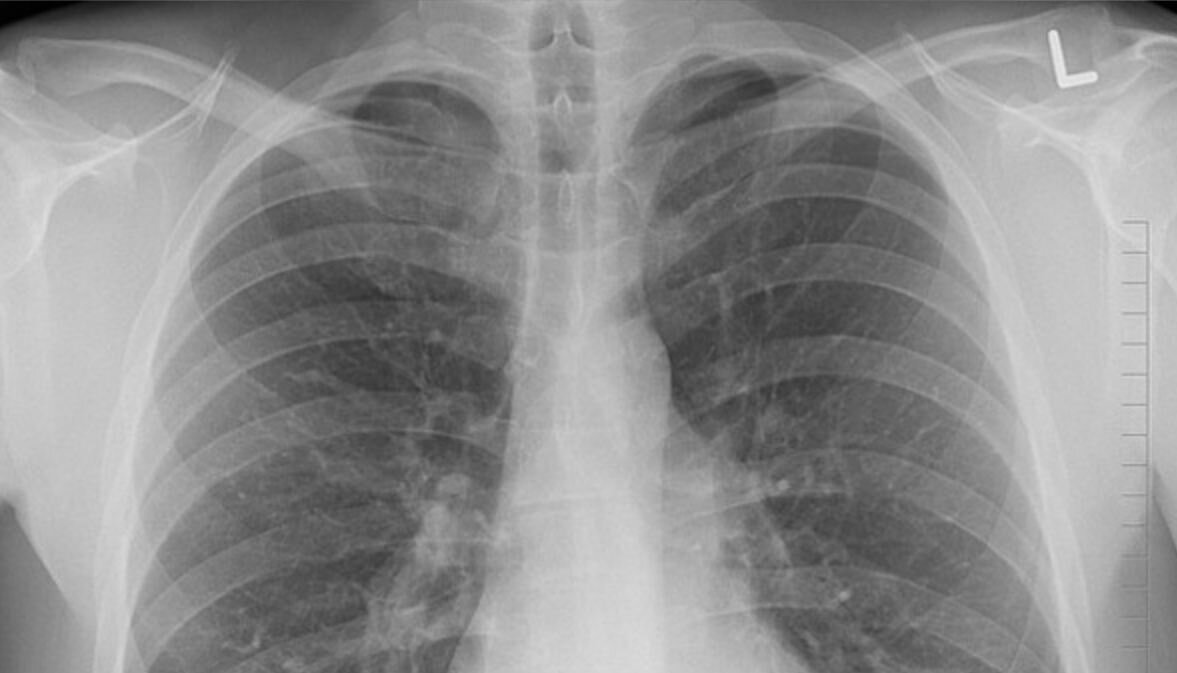

Пульмонолог рассказал, как определить признаки пневмонии

Завотделением терапии Первого МГМУ им. Сеченова, врач-пульмонолог Александр Пальман в интервью радиостанции «Говорит Москва» отметил, что пневмония обязательно сопровождается повышением температуры в течение нескольких дней.